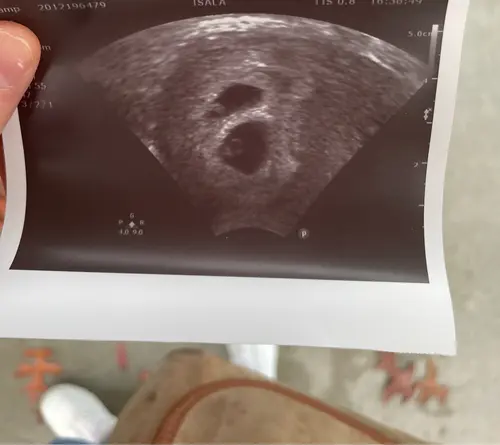

Gefeliciteerd! Ik heb vorige week m’n eerste (vroege echo) gehad. Ik ben nu 8wk zwanger van een tweeling! Heel spannend! 🫣

Hier ook een tweeling 😊 ben vandaag 8+2. Vorige week echo gehad

Hier ook een tweeling! Nu 8,5 week onderweg en al twee echo’s met twee kloppende hartjes gezien. Heel spannend allemaal!